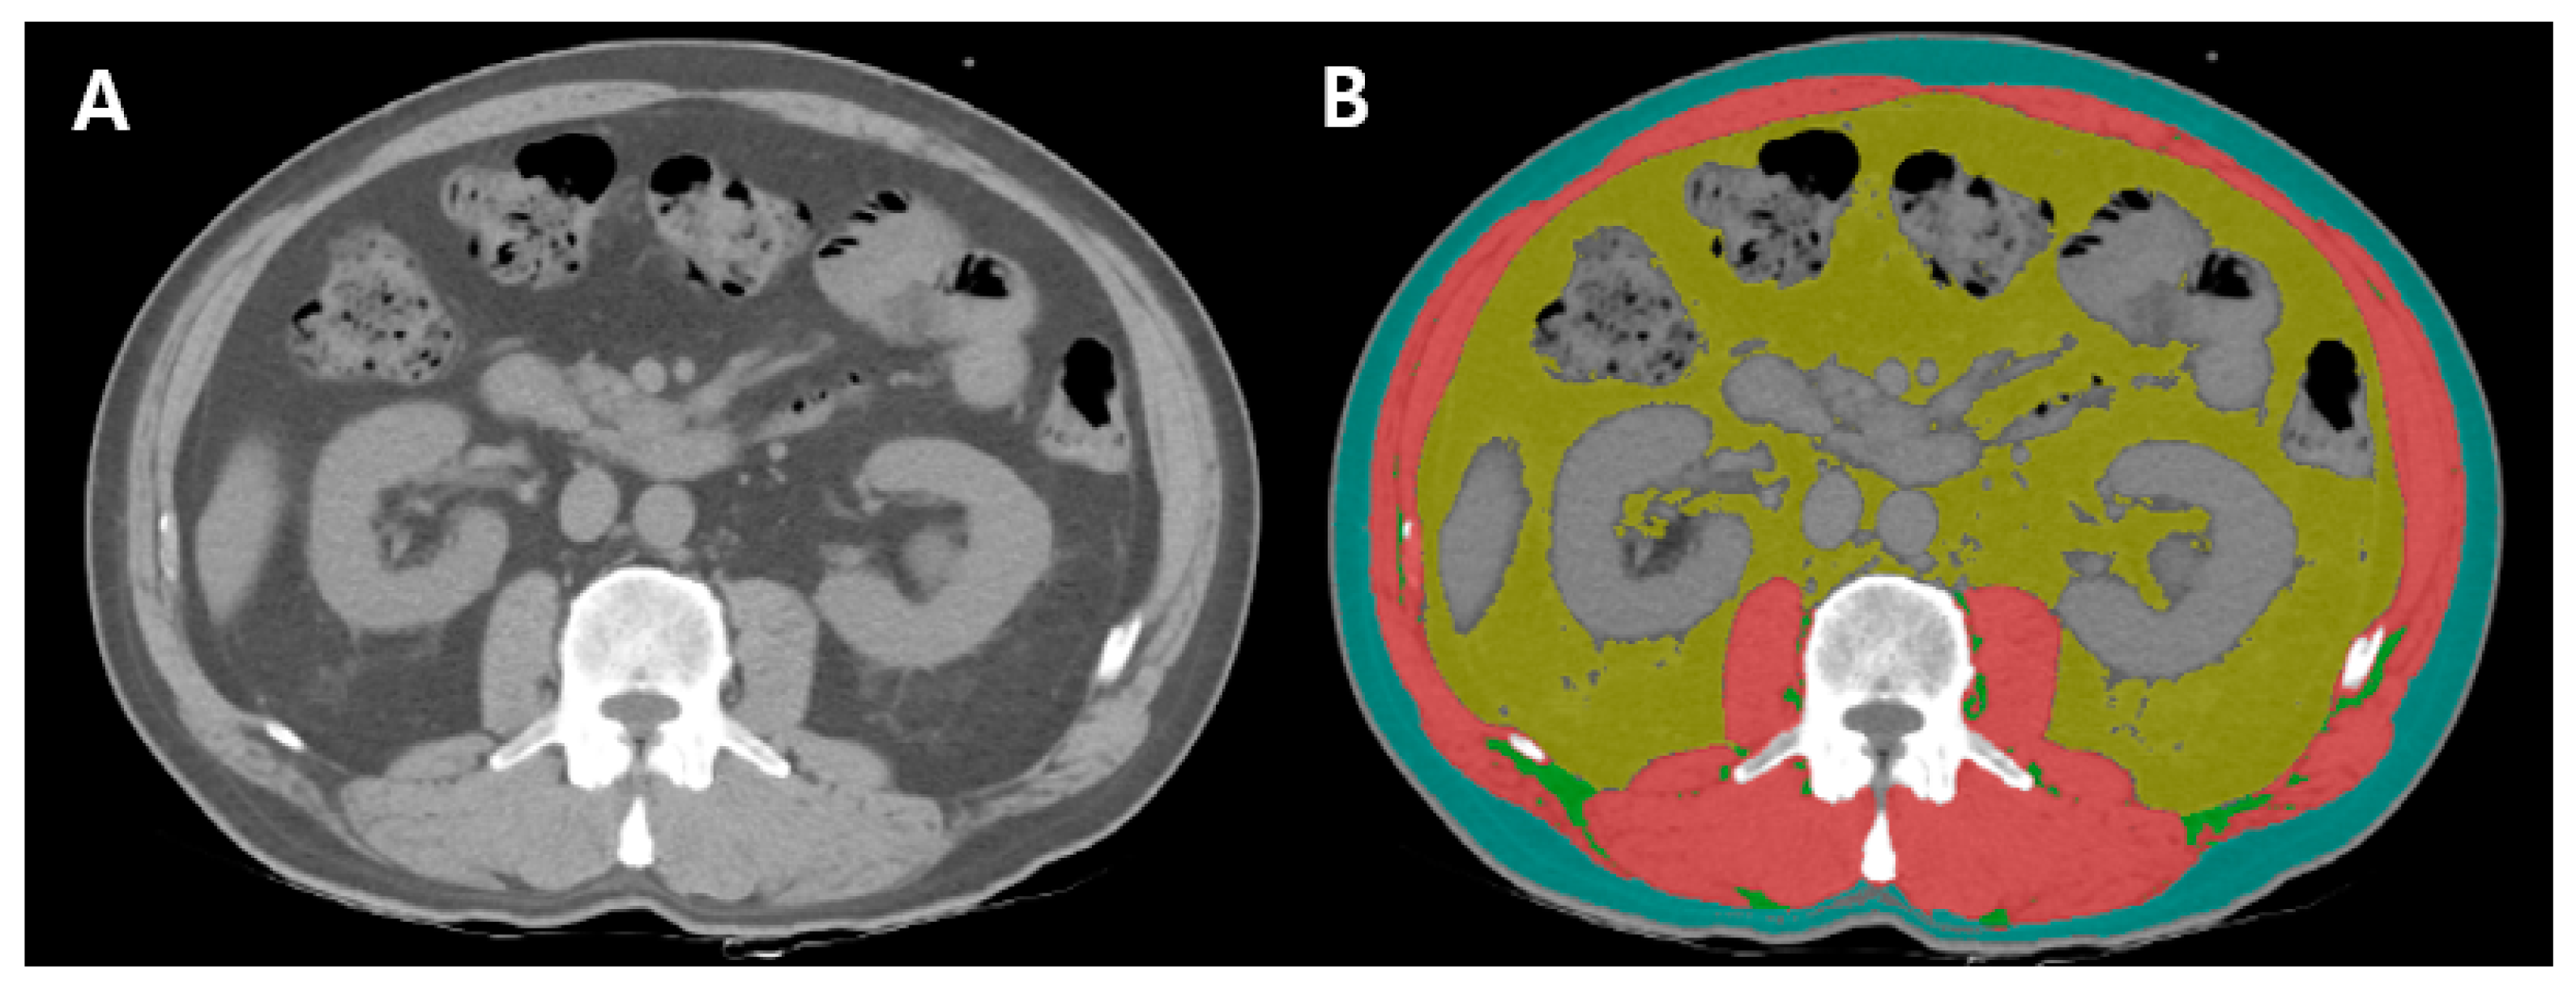

- Paris, M.T.; Tandon, P.; Heyland, D.K.; Furberg, H.; Premji, T.; Low, G.; Mourtzakis, M. Automated body composition analysis of clinically acquired computed tomography scans using neural networks. Clin. Nutr. 2020, 39, 3049–3055. [Google Scholar] [CrossRef]